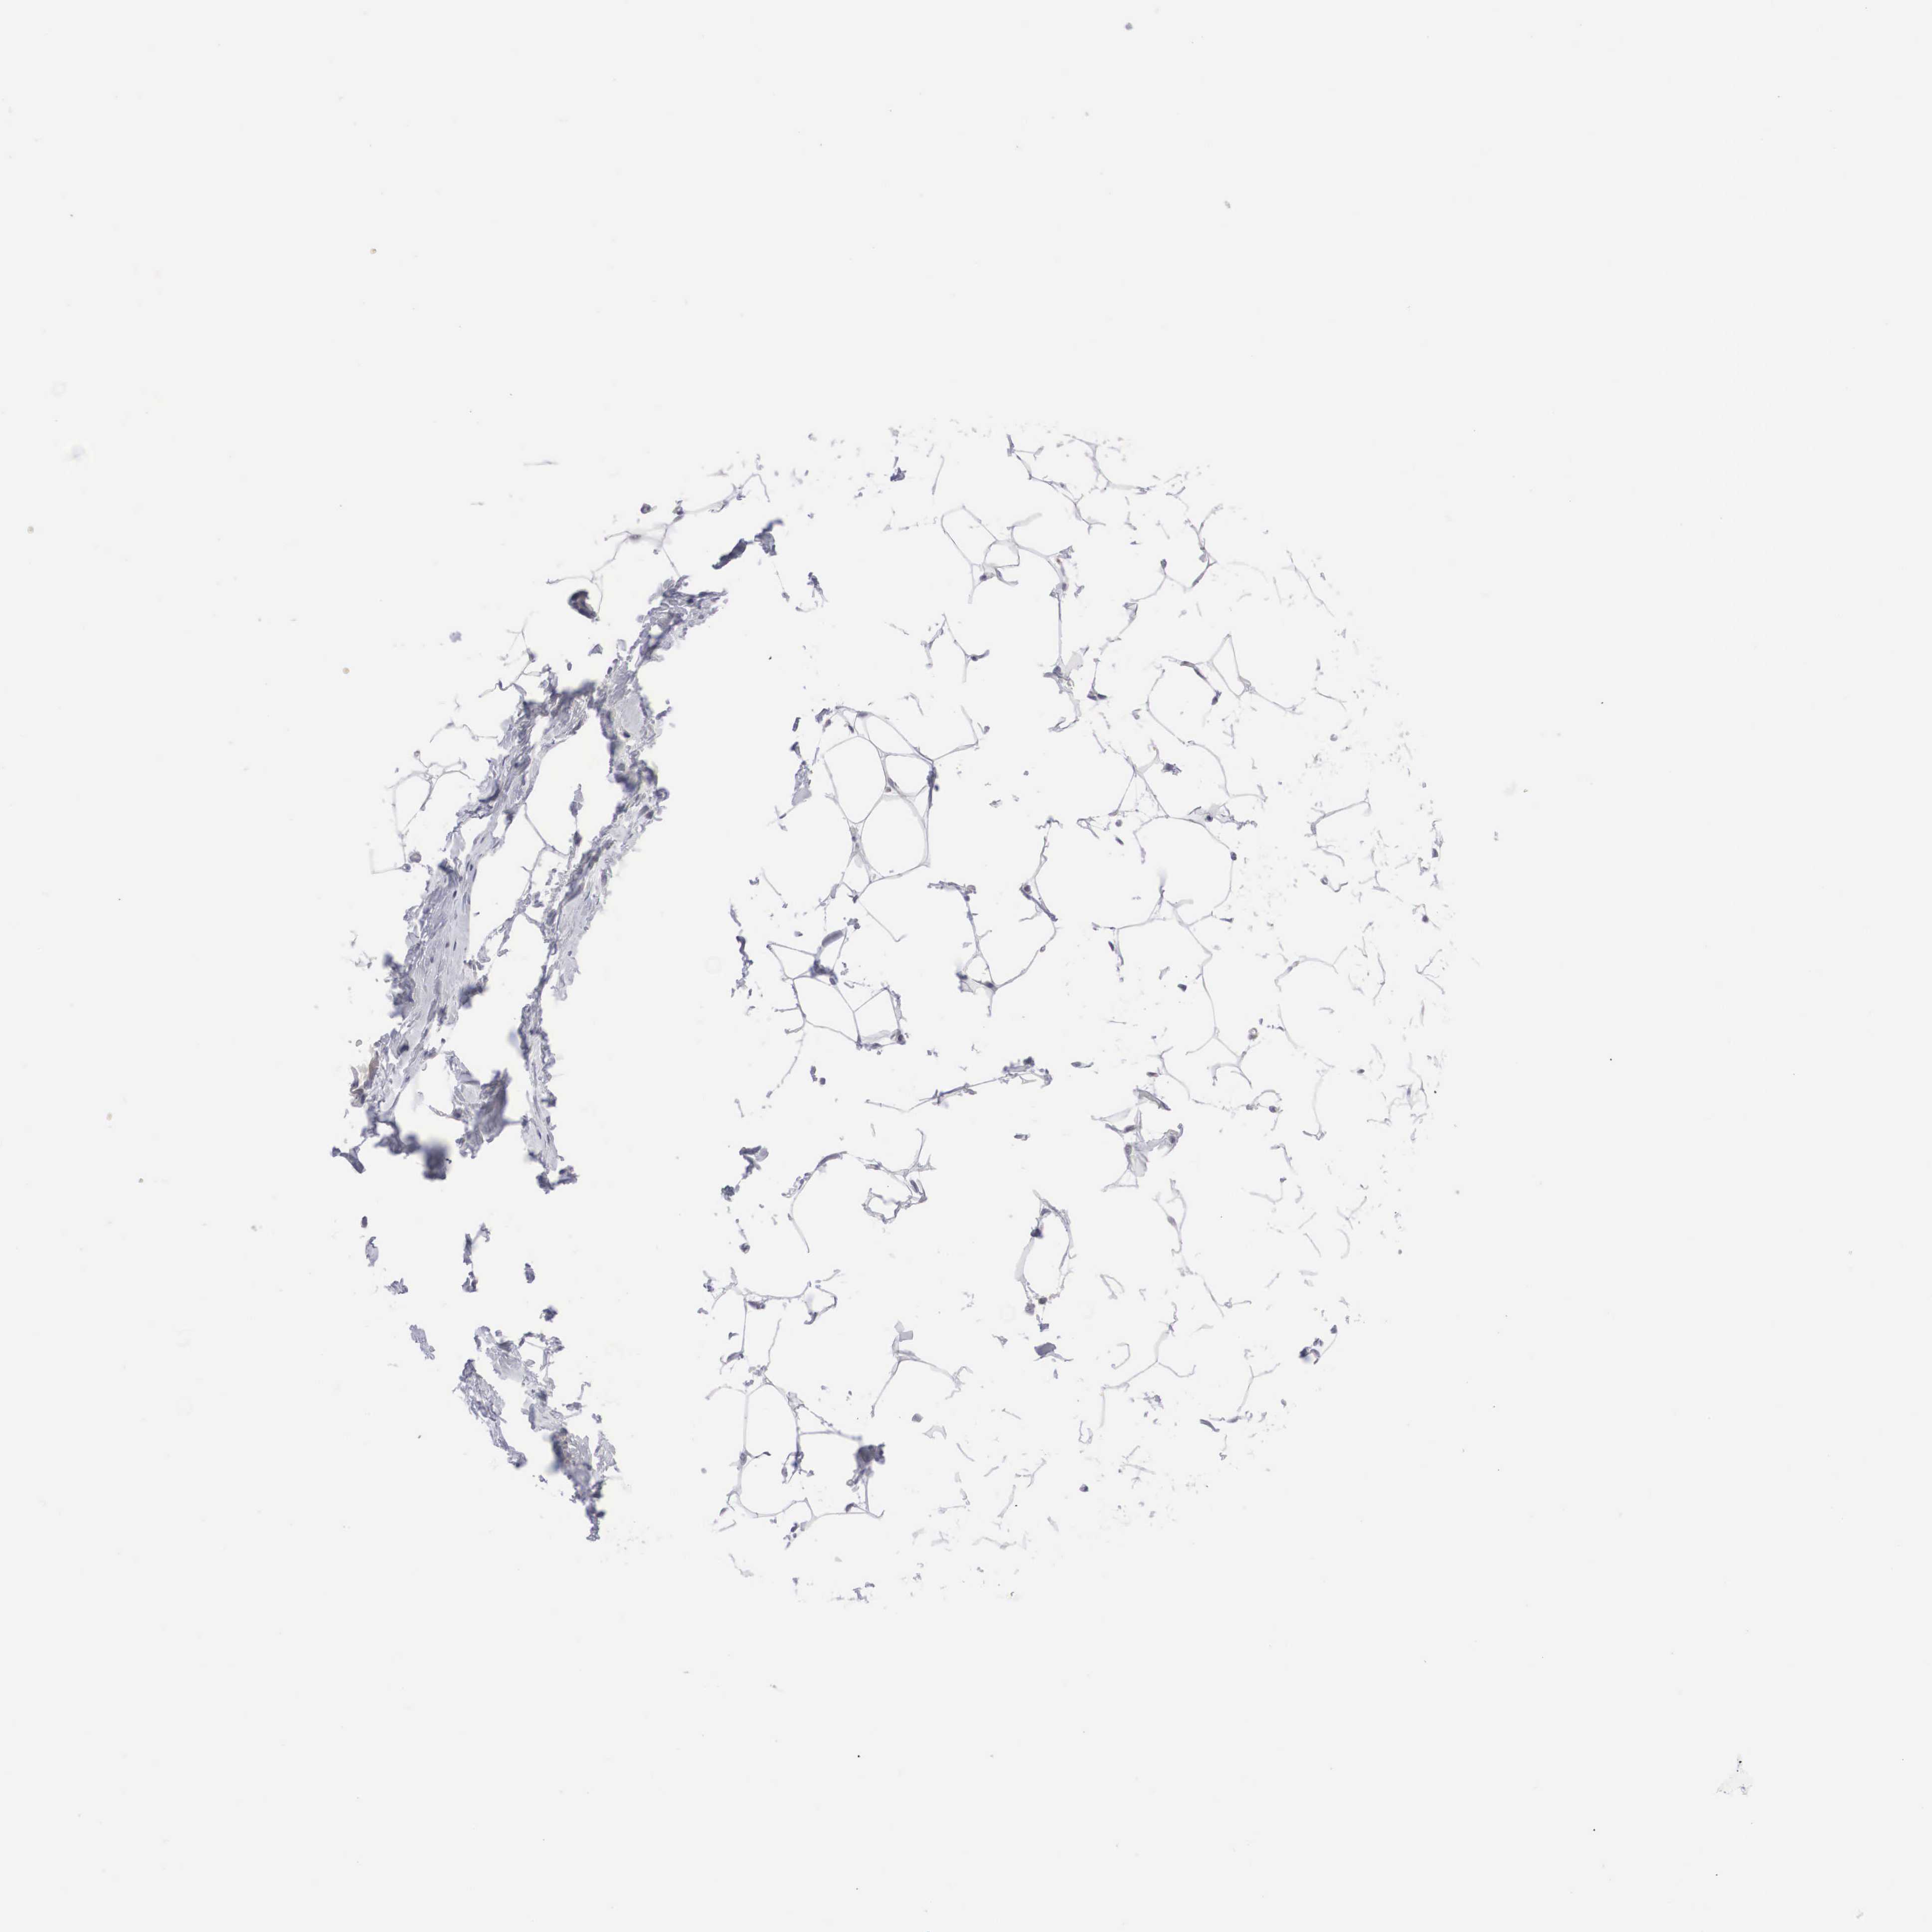

MAST4